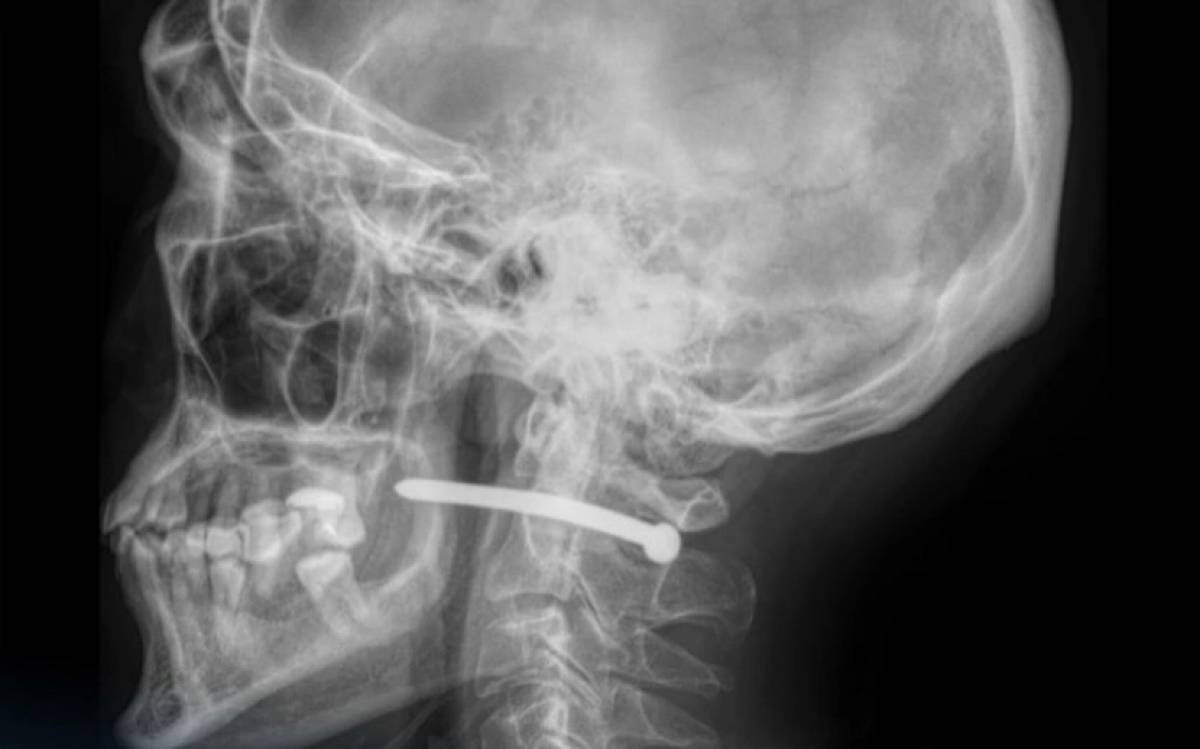

Аурухананың баспасөз қызметінің ақпаратынша, рентген-зерттеуден кейін шегенің омыртқаның мойын бөлігінен өткені анықталды. Өміріне маңызды органдары зақым алған жоқ.

"Жақсүйек-бет хирургтары жарадан шегені алып, қарап, жараны өңдеді. Жара тігіліп, стерильді таңғыш салынғаннан кейін пациентке ұсыныстар беріліп, ол үйіне жіберілді.

Мойын тұзына жарақат алу өте қауіпті – мойынның маңайынан үлкен тамырлар, нервтер, тыныс алу жолдары және жұлын өтеді. Тіпті кішкене ғана зақым алудың салдары ауыр болуы мүмкін", - делінген хабарламада.